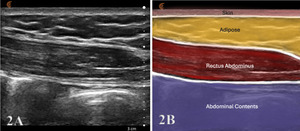

For a view of the RA in the LAX, align the transducer parallel to the rectus fibers and then sweep medial and lateral to scan the entirety of the muscle belly and note the transition to the edge of the obliques. The rectus displays a linear fibrillar echo pattern of hypoechoic contractile tissue bounded by bright anterior and posterior sheaths. Tendinous intersections appear as thin echogenic bands that traverse the muscle at intervals. Above the umbilicus, the posterior sheath is typically present; below the arcuate line it is absent—a normal transition that should not be mistaken for a defect.

To obtain a LAX view of a rectus belly, place a high-frequency linear transducer parallel to the muscle fibers, centered ~2–3 cm lateral to the LA at the level of interest (e.g., 2 cm above the umbilicus). The transducer marker faces cranially. Slide cranio-caudally to visualize tendinous intersections and the anterior/posterior rectus sheaths (note posterior sheath disappears below the arcuate line). Optimize depth so the posterior border of RA sits in the lower third of the image; set focal zone at or just deep to the posterior sheath.